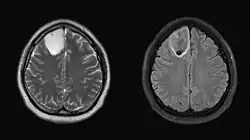

Die Bildgebung erfolgt in der Regel mittels Magnetresonanztomographie. Eine Kontrastmittelaufnahme ist bei Grad-2-Astrozytomen selten (20 %), bei höhergradigen Subtypen jedoch häufig. Verkalkungen können vorliegen. Insbesondere höhergradige Tumoren können auch ein umliegendes Ödem zeigen.[2][4][5]

Ein hochsensitives Merkmal für Astrozytome der Grade 2 und 3 ist ein T2/FLAIR-Mismatch, also ein Darstellungsunterschied zwischen zwei MRT-Sequenzen. In der T2-Sequenz zeigt sich der gesamte Tumorbereich hyperintens, also aufgehellt, während in der FLAIR-Sequenz nur der Randsaum hyperintens ist. In der T1-Sequenz ist der Tumor hypointens.[1][2][3][6]